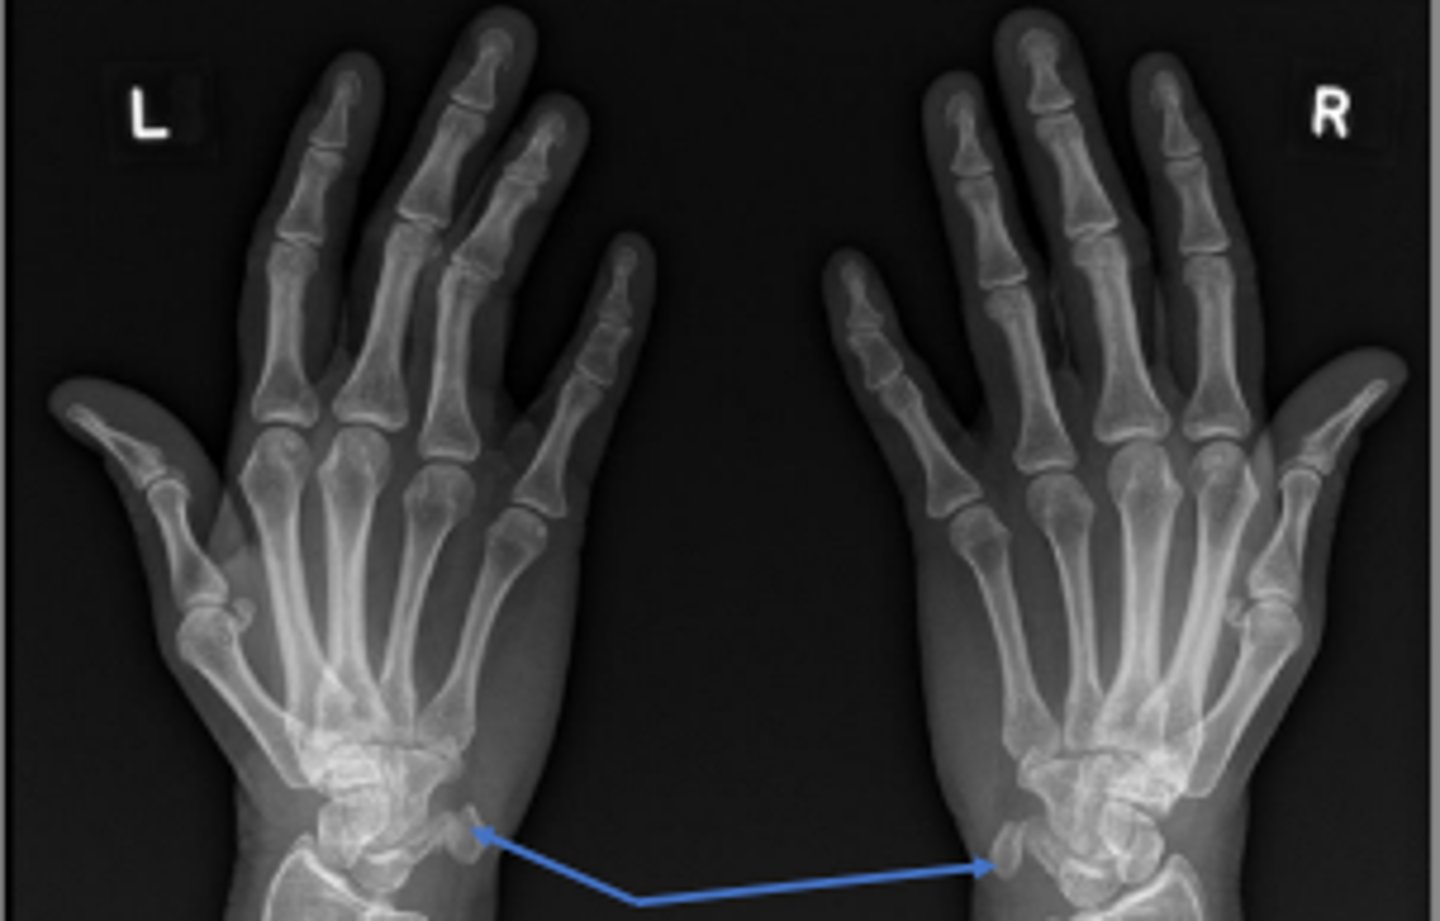

Medial oblique of the right wrist

What is the name of the radiographic view?

PA right wrist